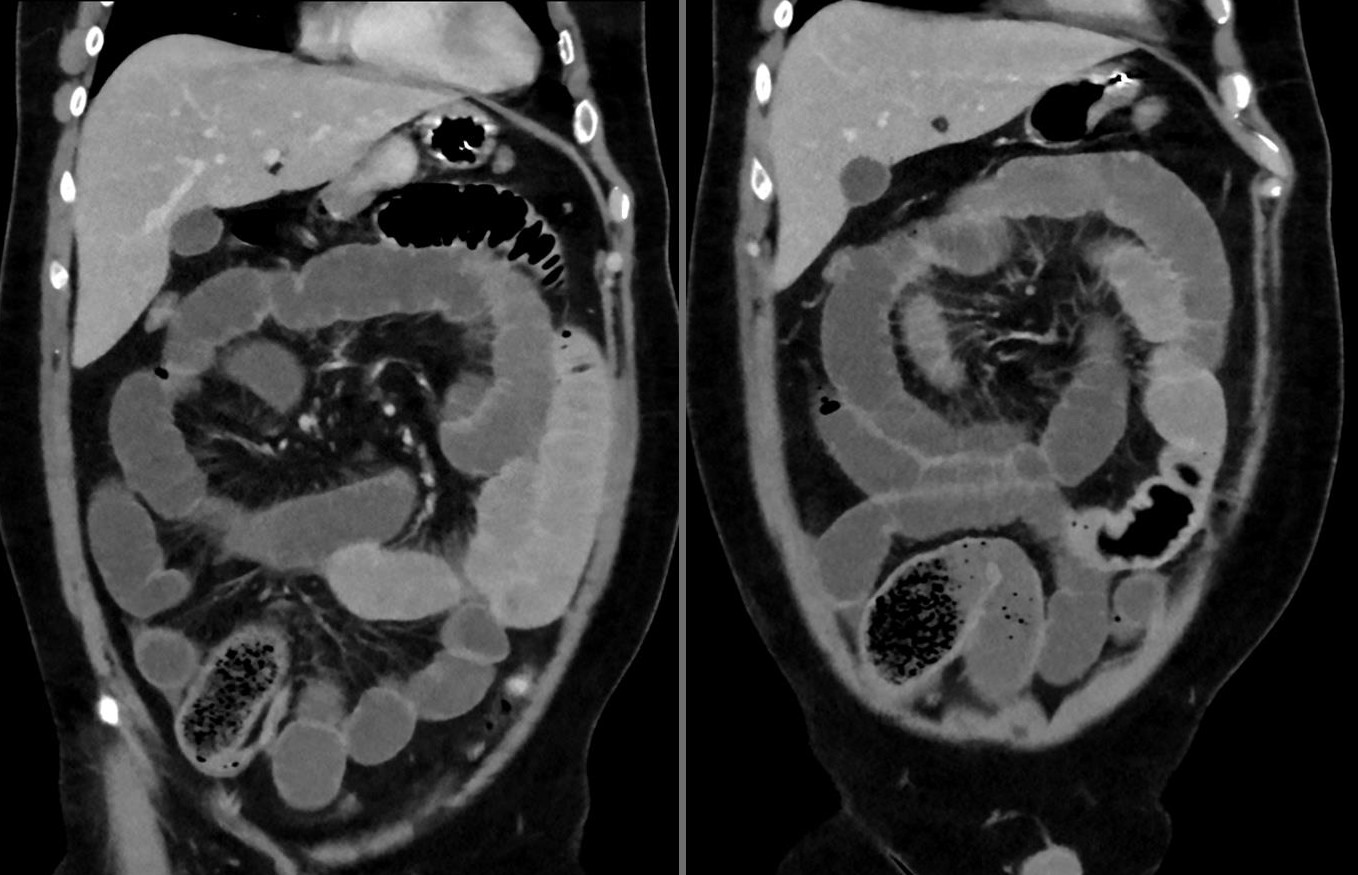

4. Die Computertomographie mit Kontrastmittelgabe hat eine sehr hohe Aussagekraft zur Beurteilung der Darmpassage und liefert auch Zusatzinformationen zu etwaigen Operationsplanung.

Dünndarmileus bei einem jungen Mann nach offenbar übermäßigem Essen von Chia-Samen. Computertomographie 2 Schichten koronar. Man erkennt den akkumulierten Bolus im unteren Dünndarm, den nachfolgenden Hungerdarm und die dilatierten, vorgeschalteten Schlingen Dünndarmileus bei einem jungen Mann nach offenbar übermäßigem Essen von Chia-Samen. Computertomographie 2 Schichten koronar. Man erkennt den akkumulierten Bolus im unteren Dünndarm, den nachfolgenden Hungerdarm und die dilatierten, vorgeschalteten Schlingen

Fig. 149 Ileus in der Bildgebung [oben: © Hellerhof, ℓ CC BY-SA 4.0; unten: © Hellerhof, ℓ CC BY-SA 3.0]#